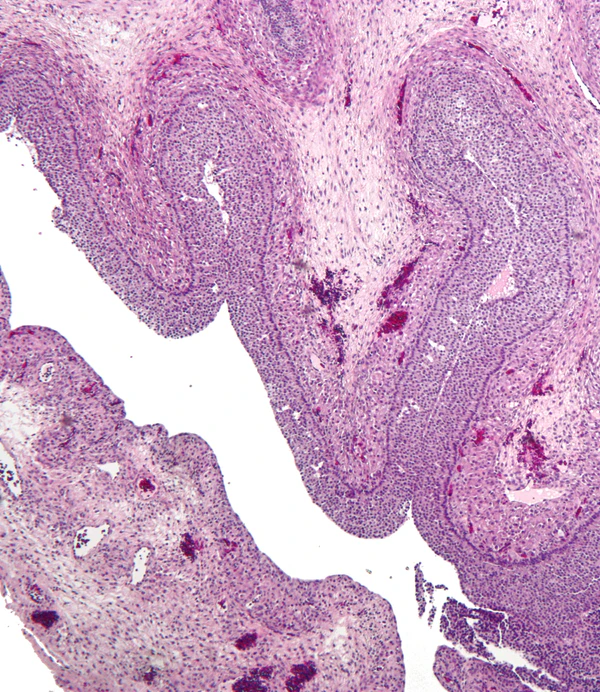

Морфологически фолликулярная киста представляет собой образование с тонкой стенкой, заполненное светло-жёлтой жидкостью и выстланное несколькими слоями фолликулярного эпителия. Наружная часть представлена фиброзной соединительной тканью. По мере роста кисты фолликулярный эпителий подвергается дистрофическим изменениям: он истончается, слущивается и подвергается атрофии. В некоторых случаях стенка кисты может состоять исключительно из соединительной ткани, выстланной изнутри плоскими или кубическими клетками[1][5].